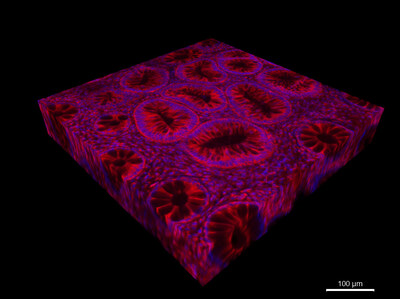

Bowel cancer is not ageist. Over the last 30 years, colorectal cancer — cancer in bowel and rectum — in people younger than 50 has become more common globally.The trend is also visible in Ireland, says Mary O’Reilly, who is pursuing a PhD in early-onset …